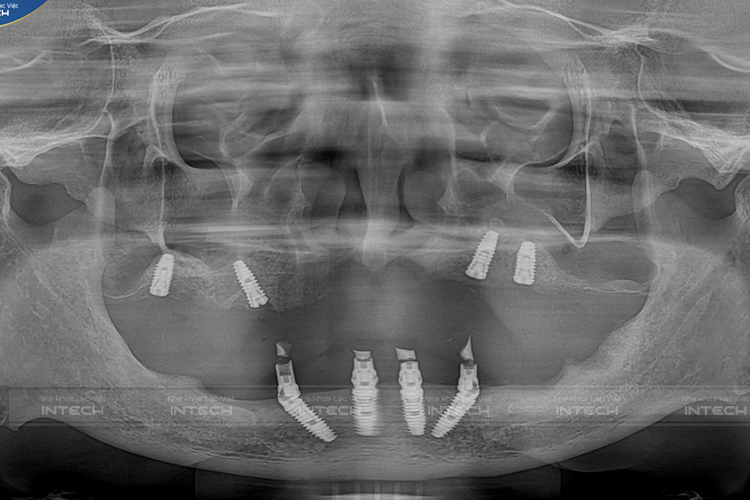

Hình ảnh phim chụp sau cấy ghép implant của chú Bình (Ảnh: Nha khoa Lạc Việt Intech)

Sau khi hội chẩn và lựa chọn được phương pháp điều trị phù hợp nhất, đội ngũ chuyên gia cấy ghép implant tại Lạc Việt Intech đã tiến hành phẫu thuật cấy ghép implant và lắp răng hoàn thiện toàn 2 hàm thành công cho chú Bình sau 5 tháng điều trị. 4 trụ implant của chú Bình tích hợp tốt, xương ghép cũng được tích hợp hoàn toàn. Các trụ implant được đặt ở vị trí tối ưu trong 3 chiều không gian và những vị trí chịu lực quan trọng trong phương pháp phục hình toàn hàm.